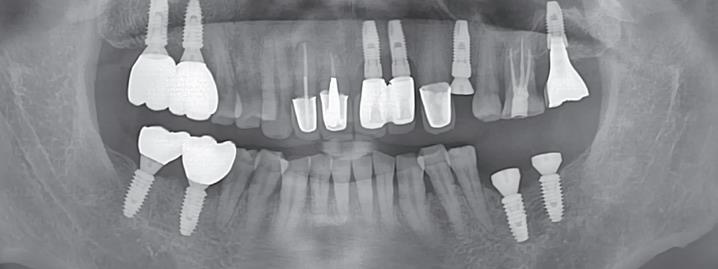

Следва да се обърне и специално внимание на лечението на усложненията и вторичните заболявания, предизвикани от зъбните импланти. В кръга на шегата по време на лекции и презентации различни специалисти говорят за лечение на лечението и за заболяване на лечебното средство - което в медицината се среща сравнително рядко, но е описано и в някои други области и медицински специалности. Изкуствените сърдечни клапи например са по-податливи към развитието на инфекциозен ендокардит в сравнение с естествените; остеосинтезните пластини могат да предизвикат костна резорбция, а протезите на крайниците - травматични невриноми. Така например на горната рентгенография се открива безпроблемна остеоинтеграция на всички зъбни импланти, но около имплантатната шийка в областта на 21 и 22 е налице костна резорбция - периимплантит. Принципно такива околошиечни костни джобове могат да не създават проблеми години наред, но понякога възпалението бързо се обостря и това принуждава пациента да търси медицинска помощ.